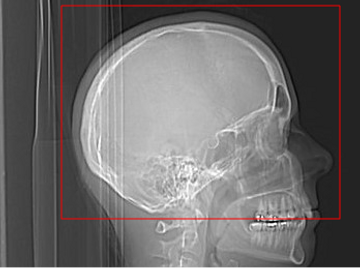

125 ml omnipaque 350 injected at 4cc/second. 40 second delay

Do Routine Head W/O 3.75x3.75 GE/3.0x3.0 Siemens bone and standard algorithms

C-2 through vertex of head

Helical: 2.5x2.0 GE standard /2.0x2.0 Siemens standard 800W 100L

Recons: 0.625x0.625 GE standard 400W 40L / 0.75x0.7 Siemens standard 400W 40L

Coronal MIP 14x4 GE/16x4 Siemens 800W 100L

Sagittal MIP 14x4 GE/16x4 Siemens 800W 100L

Oblique mip to the dural venous sinuses ( remove bone)

Coronal MPR 2x2

Sagittal MPR 2x2